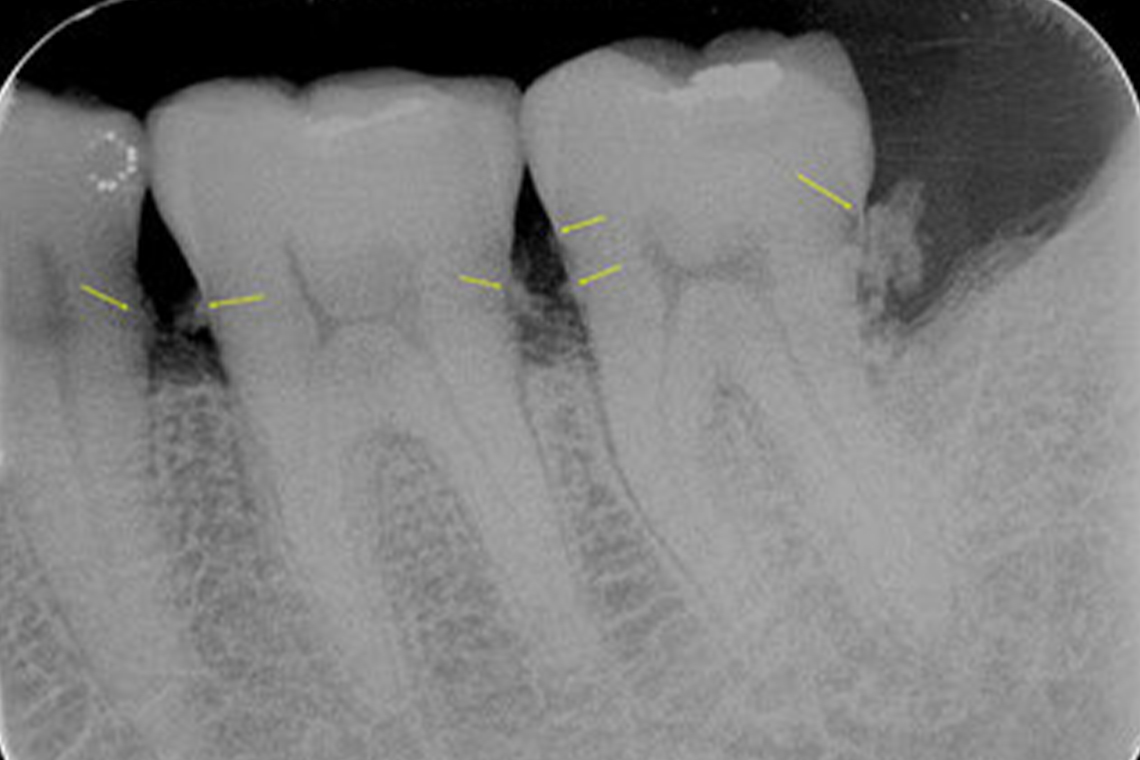

歯周病が中等度に進行している場合は、レントゲン写真による診断、そして適切な治療が必要です。レントゲン写真によって歯石の付着を確認し、隅々まで取り除いて口腔内の環境を改善します。